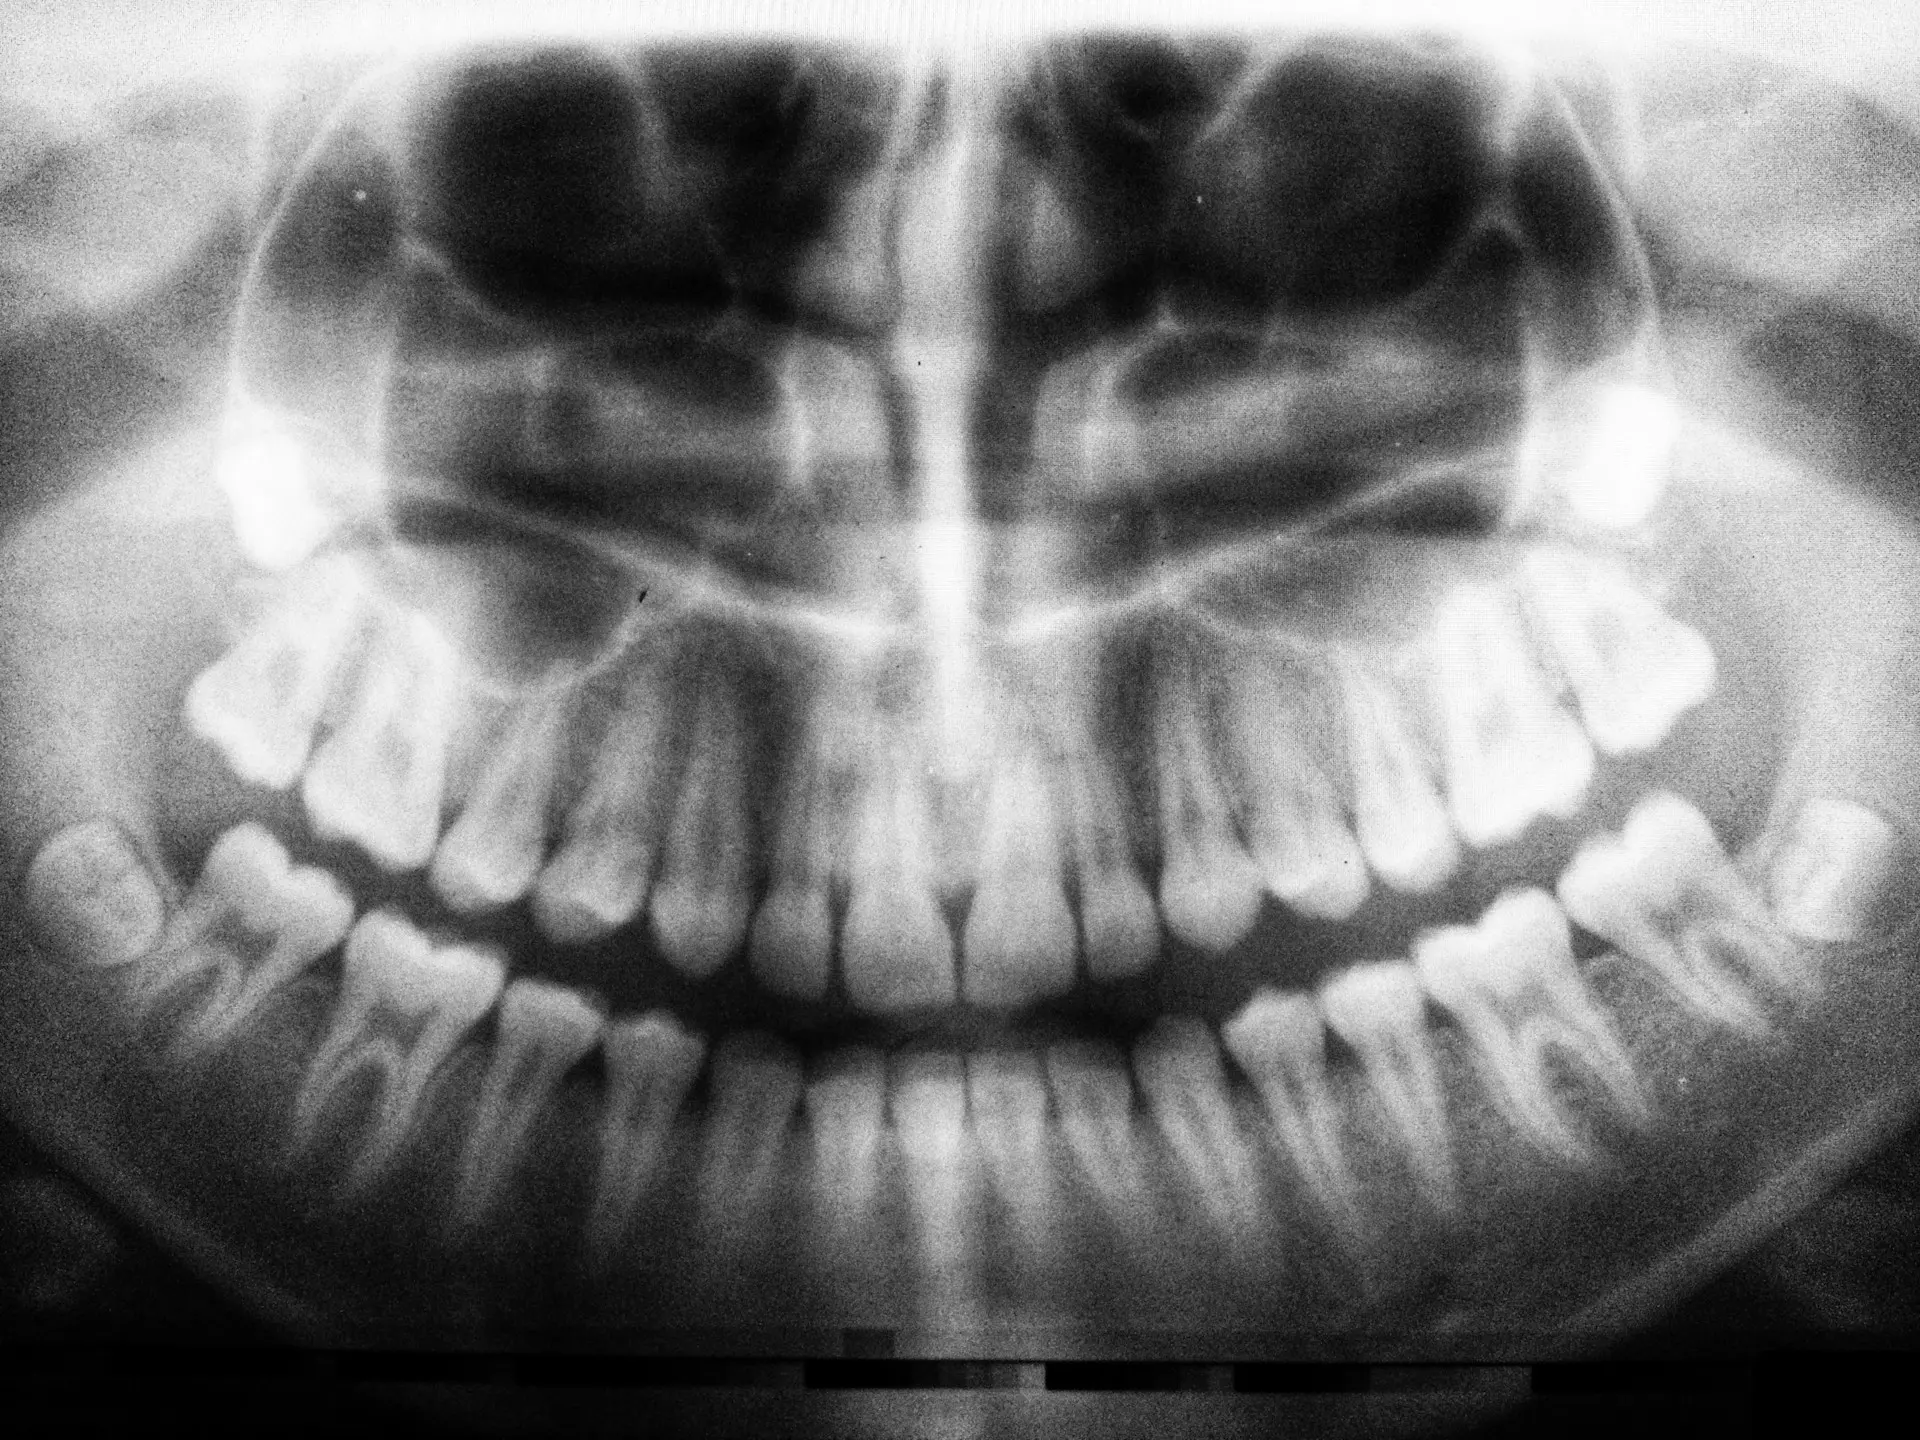

Rozpoznanie zaniku kości szczęki

Rozpoznanie zaniku kości w szczęce, jak w przypadku każdego innego schorzenia, rozpoczyna się od wywiadu medycznego. Następnie lekarz przechodzi do badania przedmiotowego – wewnątrzustnego badania stomatologicznego za pomocą lusterka i zgłębnika. Ocenia przede wszystkim stan zębów, twardych tkanek zębowych, dziąseł i błony śluzowej wewnątrz jamy ustnej, budowę i funkcję stawów skroniowo-żuchwowych. Nie mniej kluczowe w postawieniu diagnozy są badania obrazowe. Lekarz ocenia stan tkanki kostnej dzięki zdjęciom RTG i tomografii komputerowej.